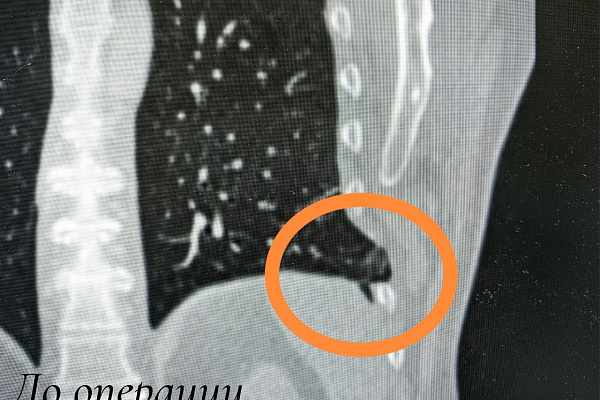

Однако два левых ребра этой естественной фиксации были лишены. При травме произошел разрыв межрёберных мышц. Это привело к образованию ложных суставов и посттравматической лёгочной грыже. Состояние сопровождалось выраженным болевым синдромом при дыхании и любом движении.